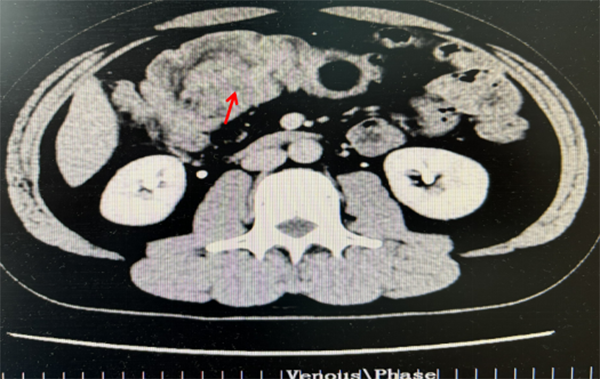

航空总医院消化病中心接诊后仔细询问查体,行便常规检查有便潜血免疫法阳性,通过电子肠镜检查时在横结肠处见一巨大粘膜下隆起凸入肠腔,表面有充血糜烂,肠腔近乎被肿物完全堵塞。超声内镜(EUS)显示横结肠黏膜下层巨大高回声肿物,脂肪瘤可能(图1)。CT检查提示横结肠巨大粘膜下肿物,约6.7cm×4.3cm,近似人体拳头大小,几乎占据整个肠腔(图2)。

图2.CT检查见横结肠巨大黏膜下肿物,几乎占据整个肠腔